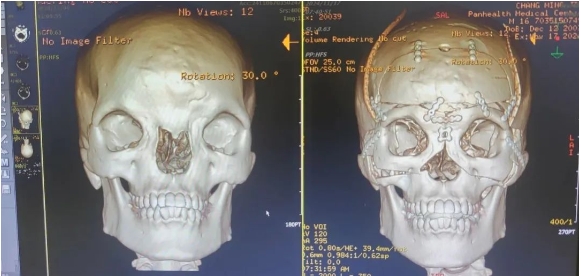

根據(jù)調(diào)查,正常男性的正常眶距平均為28mm,而初晨的雙眼內(nèi)眥角間距71mm,影像診斷報(bào)告顯示骨性眶間距55.69mm,兩側(cè)鼻骨低平、發(fā)育不良,已屬于最嚴(yán)重的Ⅲ度。

術(shù)前,整形外科劉斌團(tuán)隊(duì)聯(lián)合醫(yī)院影像中心,為初晨完善顱頜面部CT三維重建,進(jìn)行全面評(píng)估。為精準(zhǔn)的測(cè)量截骨量以防止術(shù)后復(fù)發(fā)和矯正不足,劉斌團(tuán)隊(duì)選擇利用計(jì)算機(jī)輔助技術(shù)模擬多次切割,來設(shè)計(jì)精準(zhǔn)的截骨線,從而避免可能出現(xiàn)的遠(yuǎn)期并發(fā)癥,并達(dá)到確切的美學(xué)效果。

手術(shù)非常順利,術(shù)后CT影像診斷報(bào)告顯示(如下圖),手術(shù)效果非常好,初晨?jī)裳酃切跃嚯x縮短至27mm,已在正常男性眼距范圍內(nèi)。